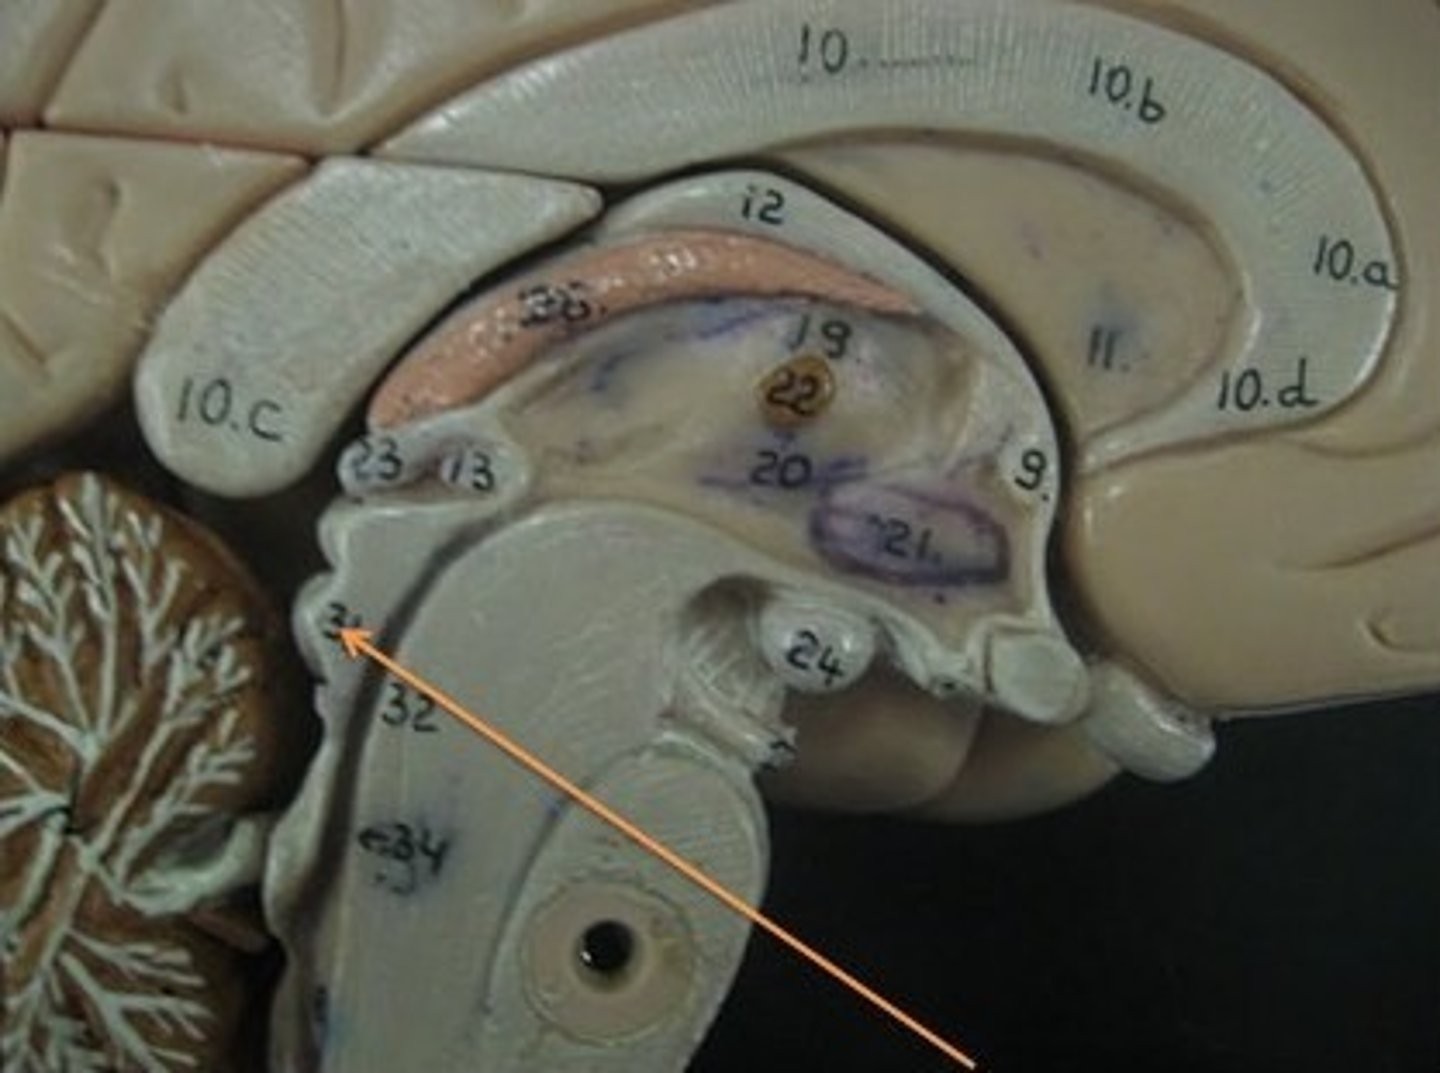

lateral ventricles

third ventricle

fourth ventricle

interventricular foramen

connects lateral ventricles to third ventricle

cerebral aqueduct

connects the third and fourth ventricles

choroid plexus

on the floor of all the ventricles, produces CSF

arachnoid villi

reabsorb/drain CSF into venous blood

diencephalon

thalamus and hypothalamus

thalamus

relay station for all somatosensory information

intermediate mass

connection between the two thalami across the third ventricle, dumbbell shape

hypothalamus

brain region (many nuclei) in charge of maintaining homeostasis

pituitary gland

produces hormones

mammillary bodies

olfactory relay stations

epithalamus

region above midbrain that contains pineal gland

pineal gland

regulates sleep-wake cycles, secretes melatonin

corpus callosum

the large band of neural fibers connecting the two brain hemispheres and carrying messages between them

septum pellucidum

membrane that separates lateral ventricles

basal nuclei

internal masses of gray matter, smooth out motor movement

fornix

band under septum pellucidum